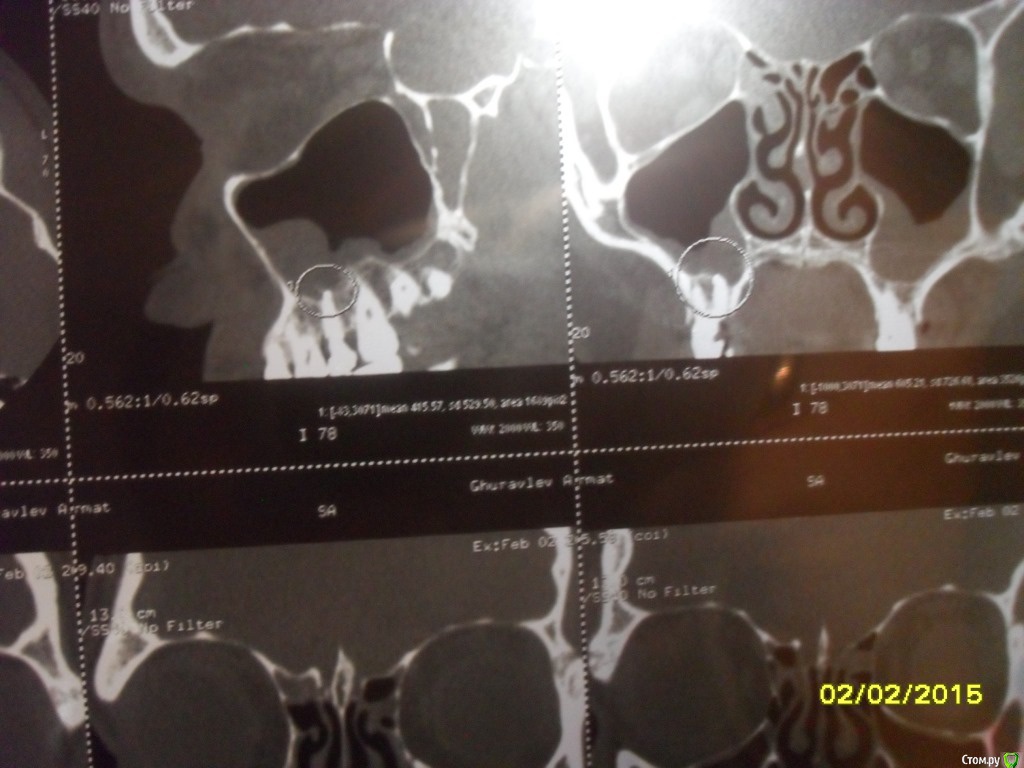

asin Опубликовано 7 февраля, 2015 Поделиться Опубликовано 7 февраля, 2015 (изменено) Добрый день всем, прошу у вас помощи или совета. Ездил на МСКТ пазух носа нашли пломбировочный материал, сломанный инструмент и кисту в правой пазухе 5 зуб. у меня его делали там штифт стоит канал пломбирован((((( мучает хронический катаральный гайморит((((( снимки прилагая может быть подскажите что мне делать.советуют дергать зуб с корнем и потом ушивать потому что откроется вход в пазуху....https://yadi.sk/d/nfWCumo7eU5ST тут образ диска МСКт... если кто то посмотрит буду признателен Изменено 7 февраля, 2015 пользователем asin Ссылка на комментарий

asin Опубликовано 16 февраля, 2015 Автор Поделиться Опубликовано 16 февраля, 2015 (изменено) надо дентальное КТ сделать, тогда будет ясно есть ли шанс перелечить зуб. Ну или сразу удалить.по рекомендации ЧЛХ удален зуб снимок прилагаю. я так понимаю пломб. мат остался.перфорация не нарушена. какую операцию рекомендуете Изменено 16 февраля, 2015 пользователем asin Ссылка на комментарий

asin Опубликовано 28 апреля, 2015 Автор Поделиться Опубликовано 28 апреля, 2015 планируется операция 1.Операция на верхнечелюстной пазухе (с применением радионожа "Surgitron", бормашины, (эндоскопически ) - удаление пломб материала2. Подслизистая коррекция перегородки носа с применением радионожа "Surgitron" расширение левого соустья и прижигание слизистой отсюда вопрос, как сложно будет достать материал именно оттуда где он лежит? Ссылка на комментарий